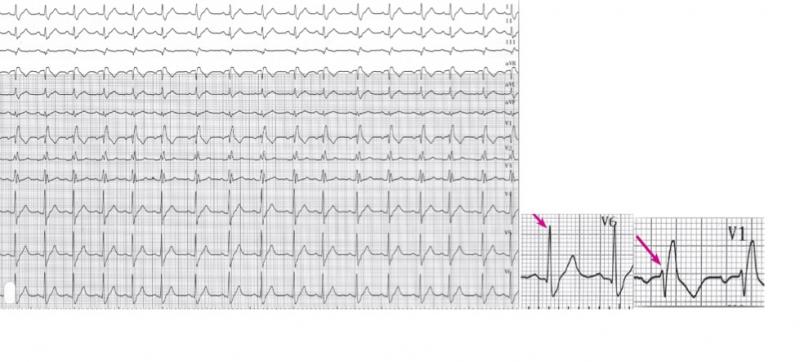

Fig 19 : Survenue inopinée d’une onde P bloquée. Il existe en RS un BBD et un HBAG avec un PR long. Il s’agit d’un BAV du second degré de type II. Il est plus grave car le témoin d’une atteinte bas située dans la jonction AV.

++++++++++++++++++++++++++++

Fig 20 : BAV de haut degré. En début de tracé relation AV en 2 :1 puis en 3 :1. Témoin d’une conduction AV altérée au niveau nodal.

A

B

Fig 21 : Dissociation AV complète. C’est un BAV du 3ème degré.A) L’échappement est haut situé car les QRS d’échappement sont fins. B) L’échappement est bas situé car le QRS est large.